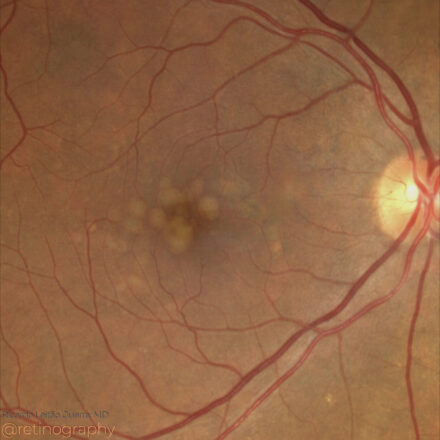

AMD: Soft Drusen

80yo

80yo In age-related macular degeneration (AMD), soft confluent drusen appear as yellowish deposits on true color imaging, often coalescing into larger lesions. Optical Coherence Tomography (OCT) reveals these drusen as elevations of the retinal pigment epithelium (RPE) with underlying hyporeflective spaces. The presence of large, confluent drusen increases the risk of […]